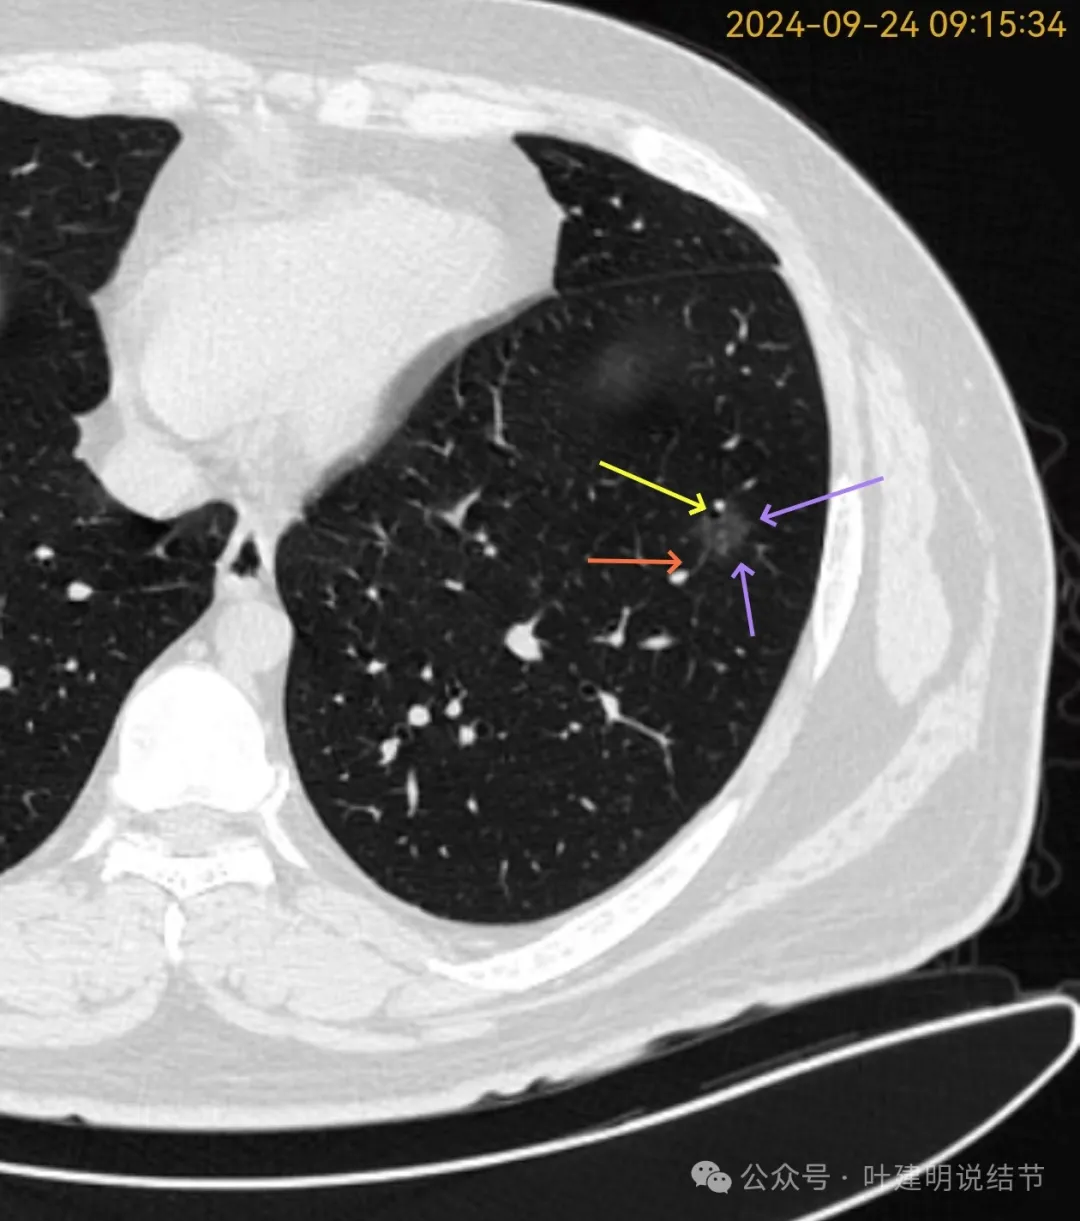

再看2024年9月复查的片子:

有毛刺征,整体轮廓清,与血管之间间隙消失。

毛刺、血管征、邻近支气管扩张、整体轮廓清,病灶与血管间隙消失。

血管弯征可见、细毛刺明显、细支气管扩张,血管进入。